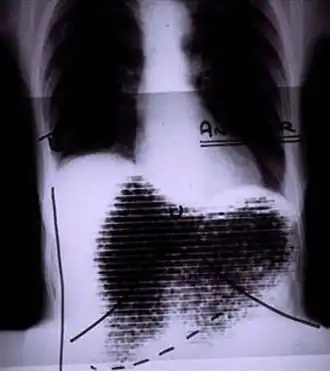

|  Manual image fusion of x-rayed and rectilinear scanned chest | |

A rectilinear scanner is an imaging device, used to capture emission from radiopharmaceuticals in nuclear medicine. The image is created by physically moving a radiation detector over the surface of a radioactive patient. It has become obsolete in medical imaging, largely replaced by the gamma camera since the late 1960s.[1][2][3]

The patient is administered with a radioactive pharmaceutical agent, such as radio-iodine which will naturally collect in the thyroid. The detector moves in a raster pattern over studied area of the patient, making a constant count rate. A collimator restricts detection to a small area directly below its position so that by the end of the scan emission from the whole study area has been detected. The output method is designed such that positional and detection information is maintained. For example, when using a light source and film the light is moved in tandem with the detector, and the intensity of light produced increases with an increase in activity, producing dark areas on the film.[11][12]